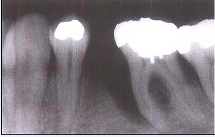

牙槽骨垂直型吸收的特点,除外()

A、牙槽骨不发生水平方向的吸收

B、牙槽骨发生垂直或斜型方向的吸收

C、与牙根面形成角型的骨缺损

D、牙槽嵴高度降低不多,而牙根周围的骨吸收较多

E、垂直吸收多形成骨下袋

A